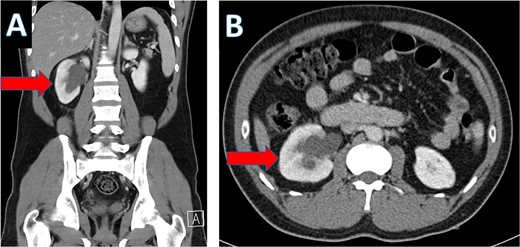

An IV contrast-enhanced CT scan of the abdomen and pelvis revealed an 8-mm proximal to mid-ureteral obstructive stone on the right side (Fig. 1), causing severe hydronephrosis of the right kidney and proximal hydroureter (Fig. 2).

CT scan showing hydronephrosis of the right kidney (A: coronal; B: axial).